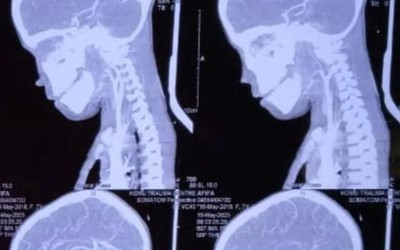

Phẫu thuật cho bé trai 7 tuổi, bác sĩ sốc nặng khi lấy ra "thứ đáng sợ"

Sự việc xảy ra khi bé trai vô tình ngã xuống đất khi đang chơi và trúng một chiếc đinh sắt, đâm xuyên qua cổ và chạm đến vùng não cực kỳ nhạy cảm.